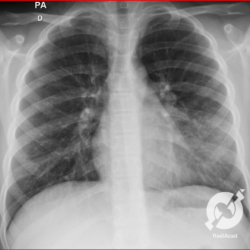

E o nome dado a esta alteração radiográfica que corresponde à substituição do ar alveolar por líquido é a consolidação alveolar.

Uma consolidação alveolar é, por definição, uma opacidade (imagem densa, branquinha) homogênea ou às vezes heterogênea (pela presença de calcificações ou cavidades), de limites mal definidos, exceto quando toca a pleura da parede ou das cissuras pulmonares. É um termo usado tanto em radiografia, como em tomografia computadorizada. Na tomografia, um outro termo é usado: vidro fosco, que é uma opacidade (branquinha mas não tanto como a consolidação), que borra o pulmão mas deixa ver os vasos de permeio (igual bigode de adolescente: dá pra ver todo o fundo).

Nós vamos mostrar aqui um pequeno apanhado de pneumonias de variados agentes, em diversos segmentos e lobos pulmonares, com extensões variadas. O objetivo é identificar o padrão radiológico de consolidação alveolar e não determinar o agente infeccioso, isso vai ser assunto para mais adiante. Aliás já antecipo que é fundamental saber localizar a lesão, porque alguns destes bichos gostam de determinados segmentos, alguns tumores também têm as suas preferências, então localização é fundamental. Se localização não fosse importante, um apartamento na beira do mar sairia o mesmo preço de um apartamento de frente pra BR-101, concordam?

Seguem alguns dos nossos casos de pneumonia para vocês treinarem os olhos e não se apavorarem nos plantões.